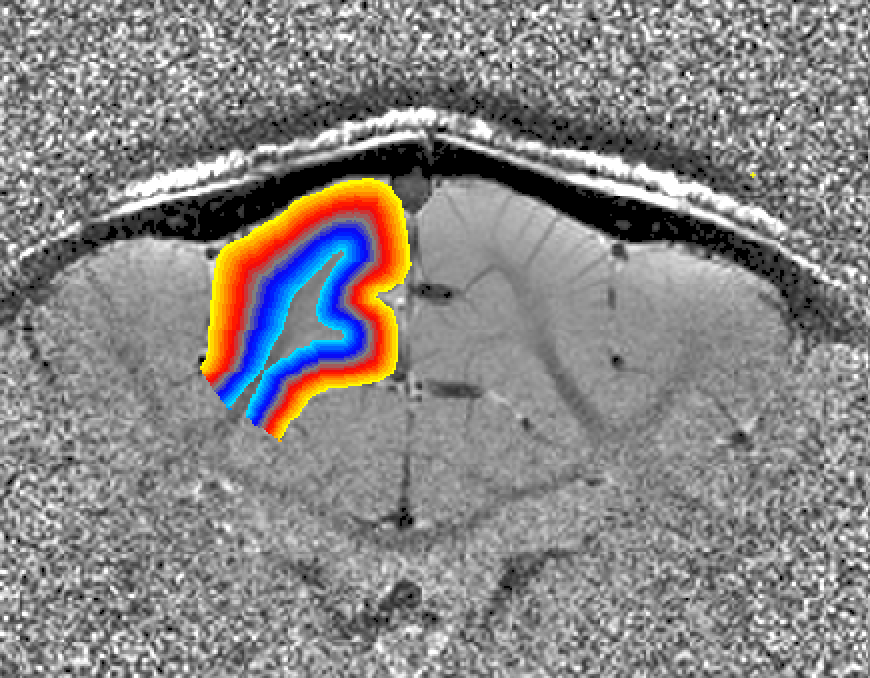

The result is a layer file layers.nii looking like this

Note on single slice data (e.g. for Shinho Cho ): when the “-threeD” flag is not set, the program LN_GROW_LAYERS estimates the layers on a slice-by-slice basis. This is done assuming that the slice direction is the third dimension in the nii header according to the default of x-y-z,as phase-read-slice. If your data are not stored like this, consider using the “-threeD” option in LN_GROW_LAYERS. Alternatively, the dimentsion can be exchanged with fslswapdim input x z y output.